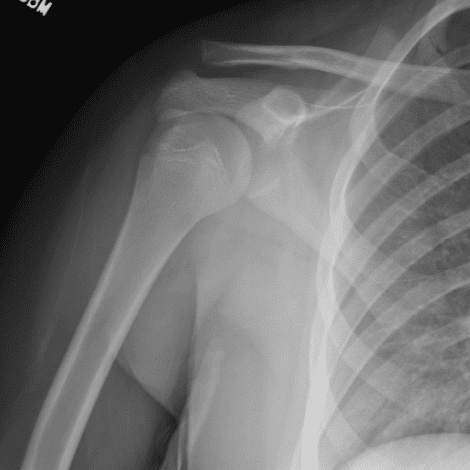

Simuliert den Dienst durch subtile oder schwierige Fälle und einige Normalbefunde.

30 Fälle